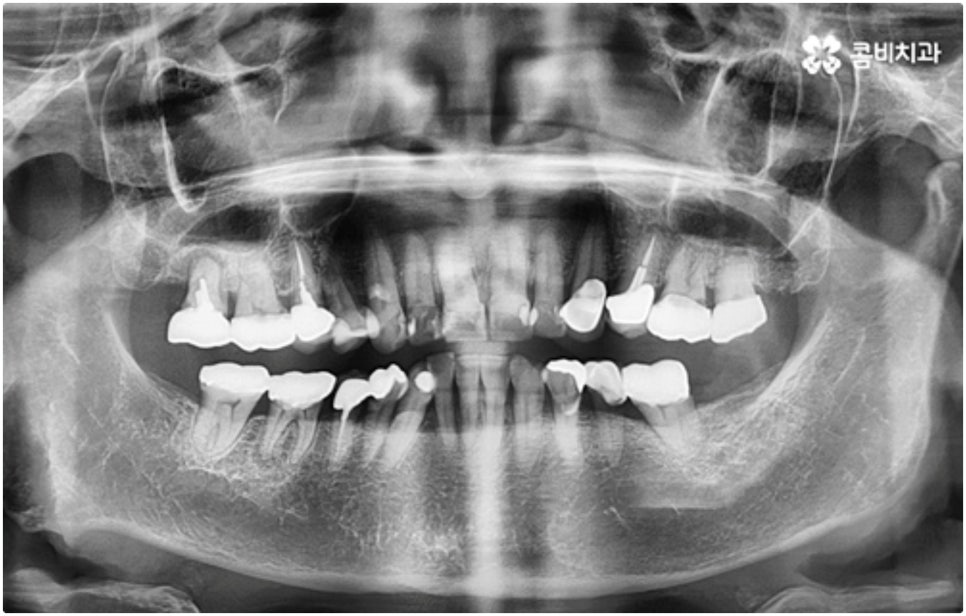

모든 치아가 위치와 모양이 제각각 다른데 특히 어금니는 구강 내 깊은 곳에 있고 주름진 저작면을 가지고 있기 때문에 관리할 때 더욱 주의할 필요가 있습니다. 꼼꼼하게 칫솔질을 해준다고 해도 음식물 찌꺼기가 남게 될 가능성이 높아 충치나 치주염 등 구강 질환이 빈번하게 발생할 수 있기 때문인데요, 이때 빠른 발견으로 초기 대처를 해주지 못하면 내부 신경까지 손상이 깊어져 치아를 발치하고 어금니임플란트 시술을 받아야 할 상황까지 발생할 수 있어요.

구강 질환 때문이 아니더라도 저작 기능의 핵심적인 역할을 담당하고 있어서 외부 충격 (실수로 딱딱한 것을 씹는 일 등) 에 노출될 위험도 큰데요, 만약 부러지고 금이 갈 때 뿌리까지 갈라졌다면 해당 어금니는 살릴 수 없고 인공 치아로 대체해야 할 거예요.

임플란트 시술이 환자분들의 잇몸뼈에 직접 고정을 시키는 방법인 만큼 개개인의 치주 상태, 구강 내부 구조 등을 면밀하게 살펴보고 치료 계획을 세워야 하며 그 밖에도 치아가 빠진 지 얼마의 시간이 흘렀는지, 장기적으로 복용 중인 약이 있는지 등 영향을 줄 수 있는 모든 관련 상황을 종합적으로 고려하여 환자분들에게 딱 맞는 어금니임플란트 시술을 무리하지 않게 진행하는 것이 중요한 체크 포인트라고 할 수 있는데요. 그렇기 때문에 먼저 3D CT를 이용한 정밀한 검사를 통해 어떤 종류의 임플란트를 어떻게 진행할지 신중하게 검토해야 하며 또한 풍부한 노하우와 뛰어난 기술력을 갖추고 있는 의료진과 함께 충분한 사전 상담을 하실 필요가 있습니다.

이와 같이 상악의 경우 상악동과 비강저(콧구멍 바닥)까지의 거리 및 신경과 혈관분포, 하악의 경우 하치조 신경 및 하치조관과 이공까지의 거리, 주위 조직 등에 대한 면밀한 검진과 파악이 필요하기 때문에 임플란트 시술을 진행할 때 상하악골 및 주변 조직을 해부학적으로 자세히 체크할 수 있는 정밀 장비 및 담당 의료진의 숙련도가 굉장히 중요한 요소라고 할 수 있어요.